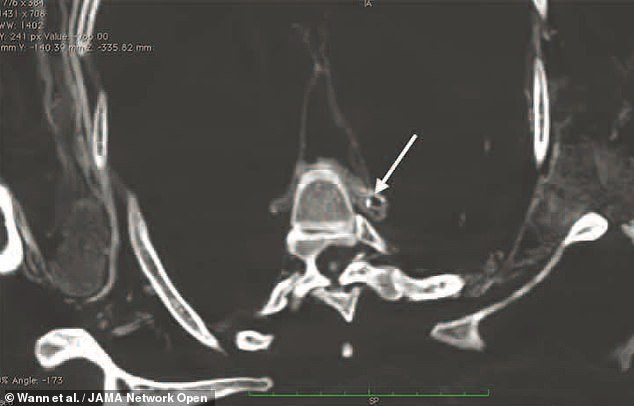

Dù có chế độ ăn giàu axit béo omega-3 nhưng những người Inuit trên vẫn bị tắc nghẽn động mạch.

Điều này khiến các chuyên gia không khỏi tò mò vì sao những người Inuit lại mắc căn bệnh trên dù có chế độ ăn uống được đánh giá là tốt cho sức khỏe.

Vì vậy, các chuyên gia dự kiến tiến hành một số kiểm tra khác nhằm tìm ra nguyên nhân khiến người Inuit mắc bệnh về tim mạch.